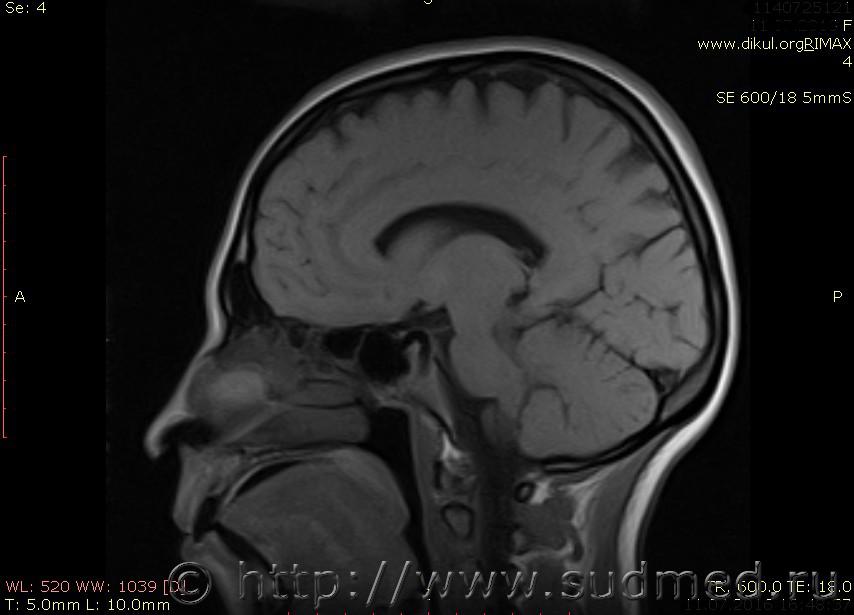

МРТ головного мозга показало: МР-данных за наличие очаговых изменений в веществе головного мозга на момент исследования не выявлено. МР-признаки нарушения соотношения в атланто-осевом суставе. Определяется ассиметрия положения зубовидного отростка С2 относительно боковых масс С1(справа 6,5; слева 4 мм.)

впрочем. есть и еще один момент - вывих С1! который не звучит в диагнозе невролога, хотя этот вывих - тяжкий вред здоровью.

Сама по себе эта информация даёт основания подозревать вывих первого шейного позвонка, но однозначно не свидетельствует о наличии вывиха. Нужно смотреть на снимках наличие реакции со стороны мягких тканей, в т.ч. связочного аппарата, нужно анализировать особенности неврологической патологии, её динамику и проч.

Запрошен электронный вариант снимков из учреждения, где делалось МРТ. Т.к. с самого снимка делать копии не получается,очень мелкие кадры. Завтра попробую вставить в сообщение. (Но СМЭ снимок не смотрел, смотрел только мед.карту, в которой находилось описание МРТ).

Посмотрите пожалуйста снимки, надеюсь на них видны позвонки С1,С2?